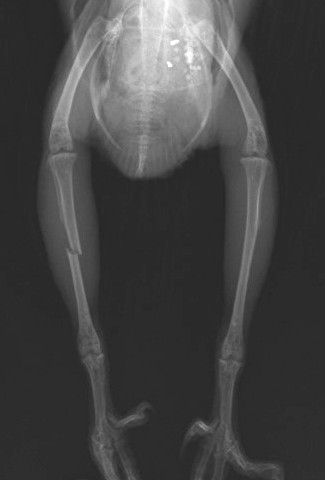

ももちゃんのレントゲン写真です。右脛足根骨が骨折しているのが分かります。